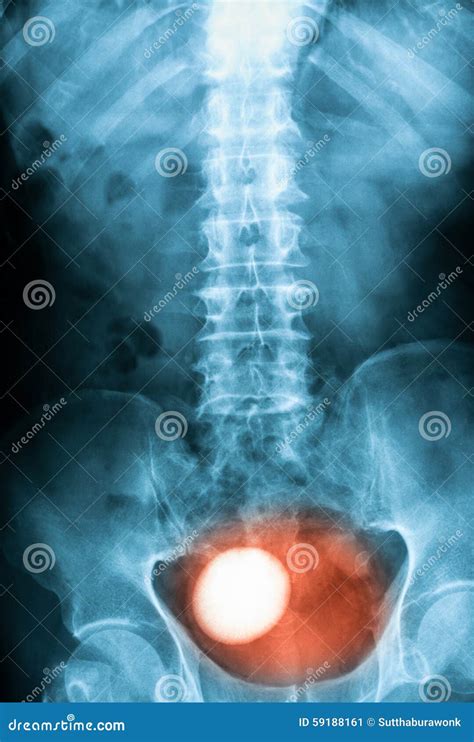

A Kub Abdominal X Ray, also known as a KUB (Kidneys, Ureters, Bladder) X-ray, is a type of abdominal radiograph that provides a detailed view of the abdominal cavity. This imaging technique is commonly used to assess the organs and structures within the abdomen, including the kidneys, ureters, bladder, intestines, and other soft tissues. The primary goal of a Kub Abdominal X Ray is to detect abnormalities such as obstructions, infections, or tumors.

• Calcifications or stones in the kidneys or bladder

Kidney Stones Calcifications in the kidneys that can cause severe pain and urinary tract infections.